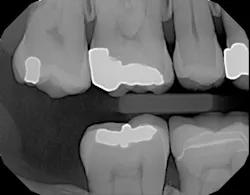

Here's another example of where a patient benefited from this technology's ability to accurately display interproximal caries.1 The patient needed a crown on tooth No. 3, and adjacent tooth No. 2 looked clean on a bitewing x-ray (figure 5).

Figure 5: Bitewing x-ray shows no indication of caries on tooth No. 2Before I began prepping for the crown, I used CariVu. On the images, I saw not only a crack on the tooth that was to be crowned, but also clear caries on the adjacent tooth (figure 6). During treatment, I snapped a picture of the preparation on tooth No. 2 with an SLR extraoral camera (figure 7). I took an additional photo mid-treatment to show how far the cavity had progressed into the dentin. The bitewing didn't show any of this decay. This caries detection technology gives me a great opportunity to tell patients that I found a cavity that we would not have known about until it caused trouble. There is no surprise later and no apologies for missing an early lesion.